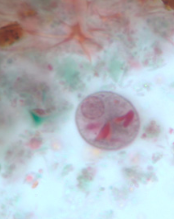

Professor: Dr. Glena Fe A. Yapchulay-Alcabasa

ENTAMOEBA HISTOLYTICA WITH CHROMATID BODY